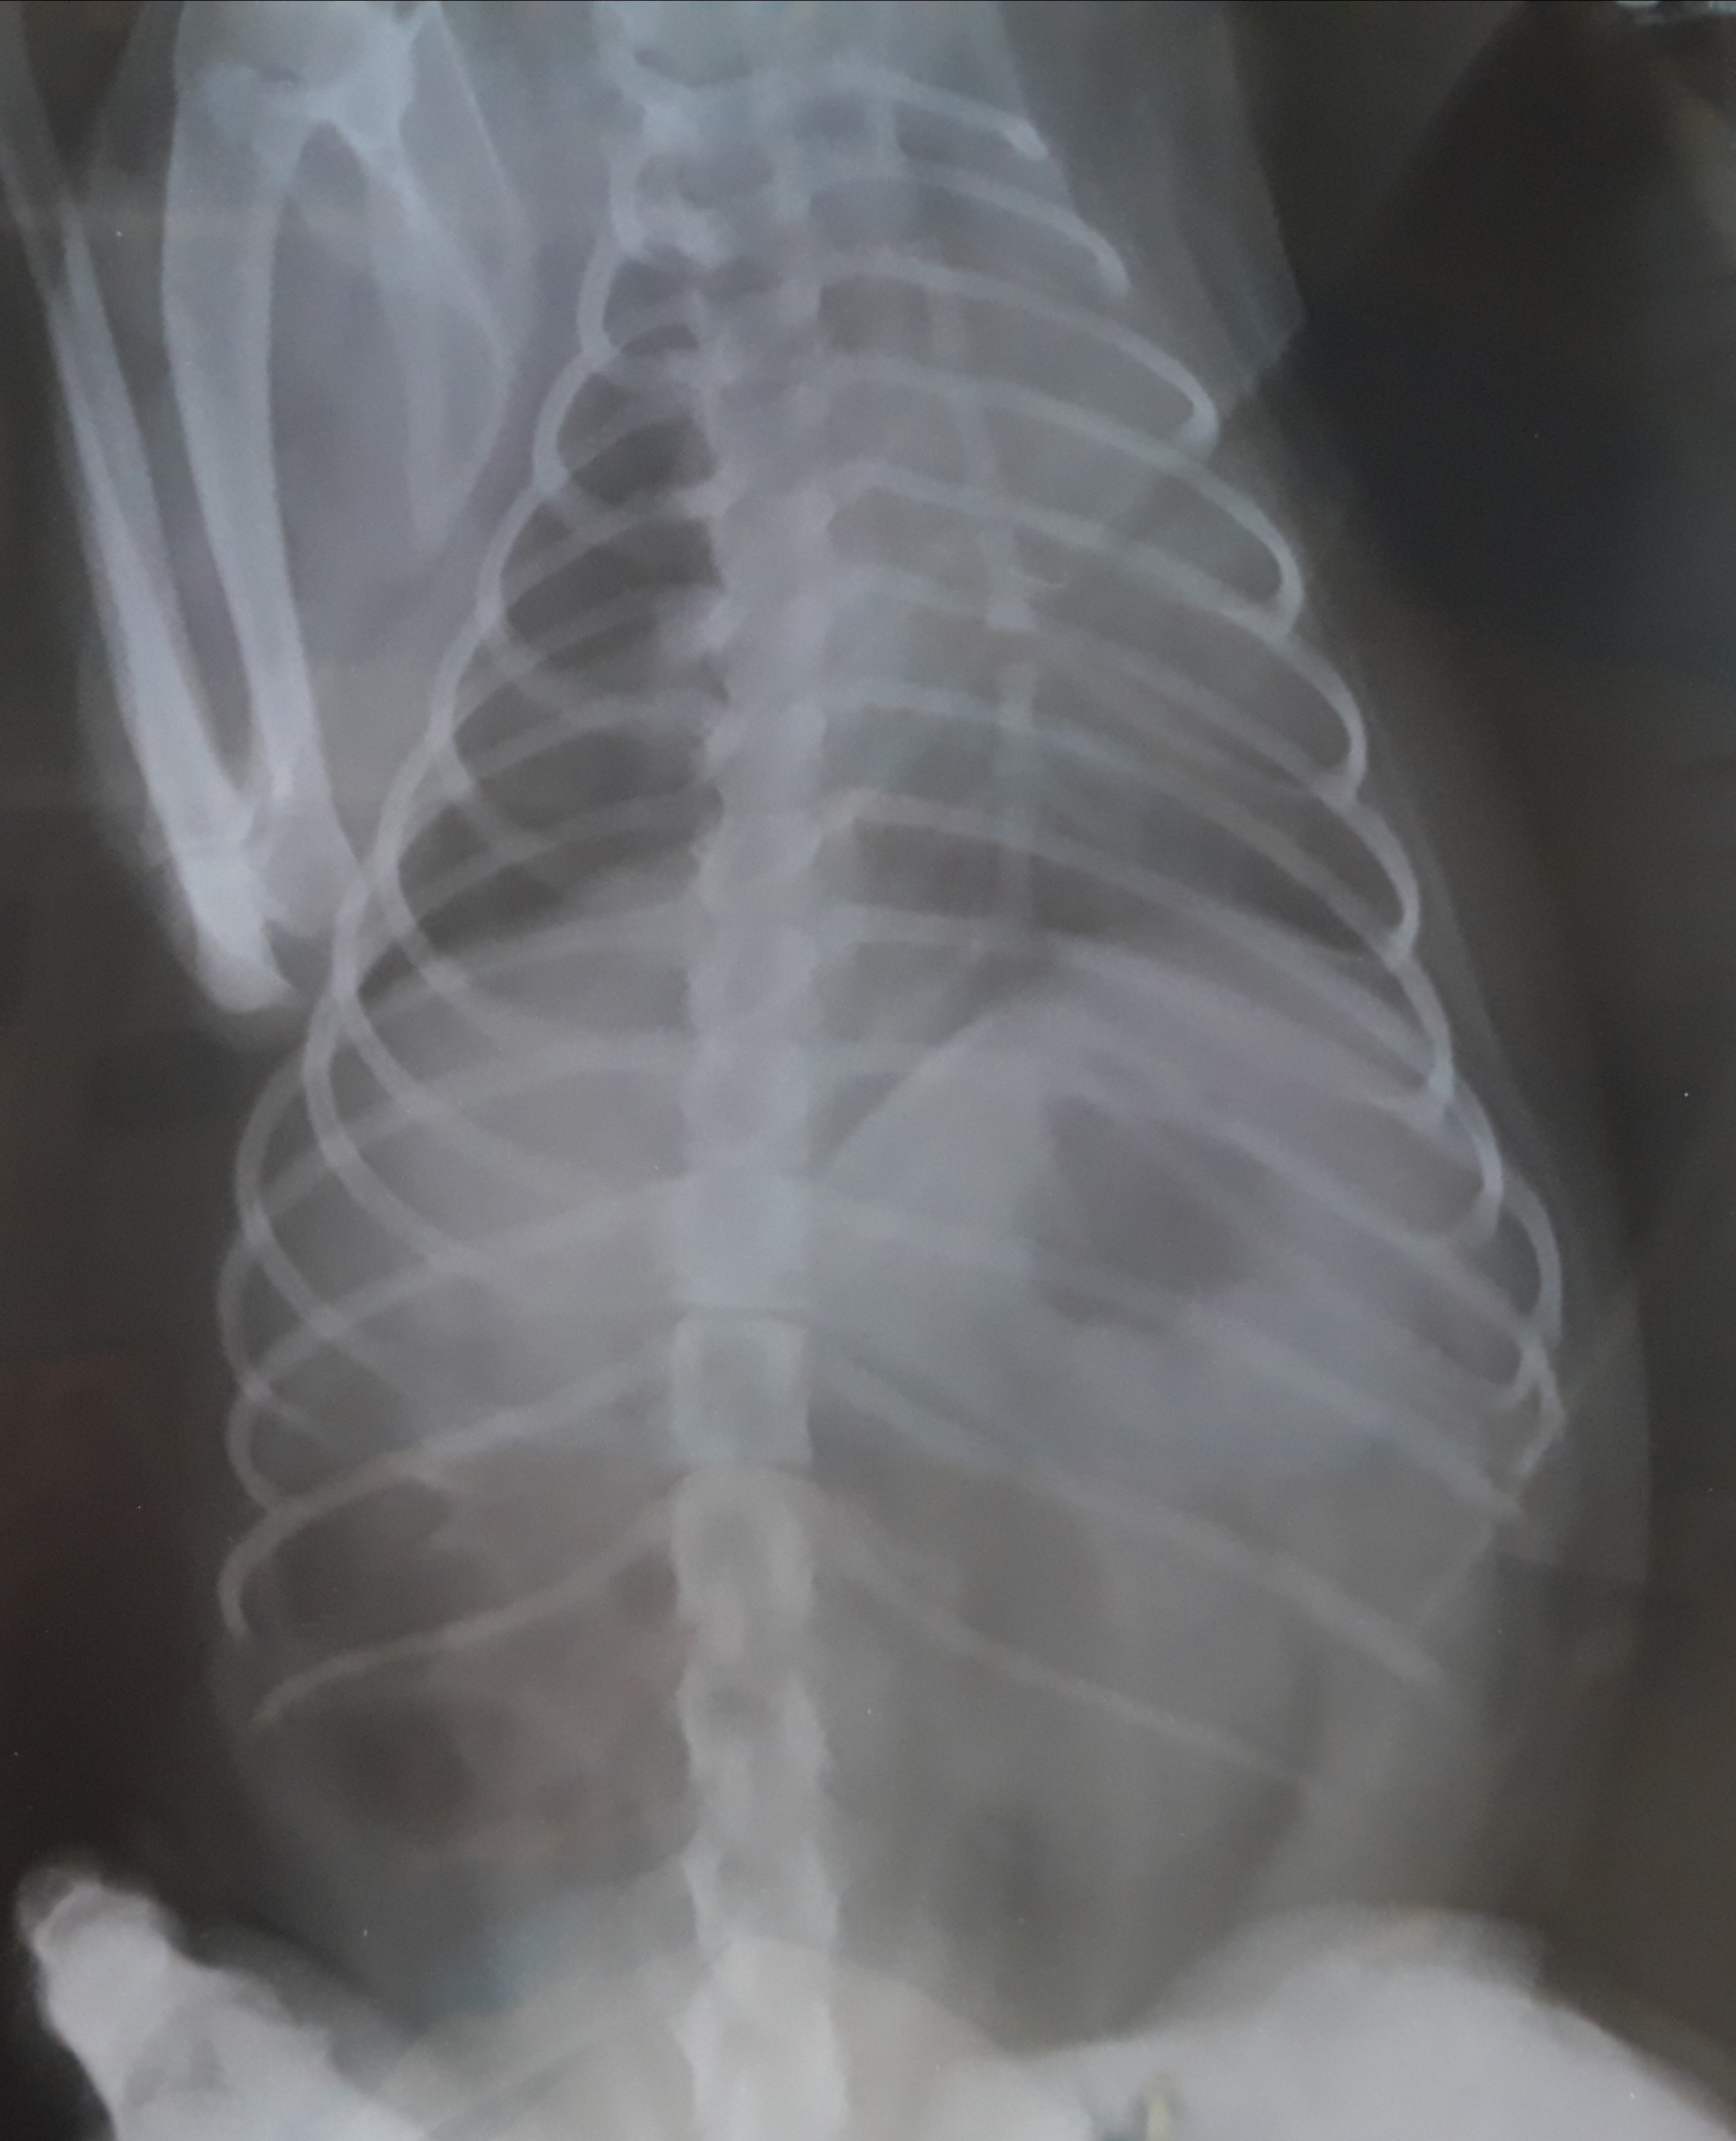

Вот еще один, но он кривой сказали

Может это я так фотографирую еще, они все отсвечивают...

По снимку слева не исключают наличие жидкости, но вечером и справа уже слышали приличные хрипы.